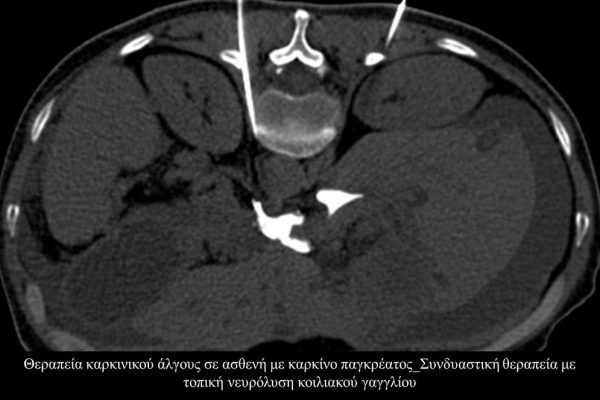

Η αντιμετώπιση του καρκινικού πόνου, εκτός από την κλασική συντηρητική φαρμακευτική θεραπεία, όταν ο πόνος επιμένει ή όταν οι παρενέργειες των φαρμακευτικών μεθόδων εξαντλούν τον ασθενή, περιλαμβάνει ελάχιστα παρεμβατικές τεχνικές με τις οποίες επιτυγχάνεται διακοπή ή καταστροφή της νευρικής οδού μεταβίβασης του πόνου. Η επεμβατική ακτινολογία διαθέτει μια πληθώρα θεραπευτικών τεχνικών που σκοπό έχουν να προσφέρουν ποιοτική βελτίωση της ζωής και των σχέσεων, τόσο των ογκολογικών ασθενών, όσο και των οικογενειών τους.